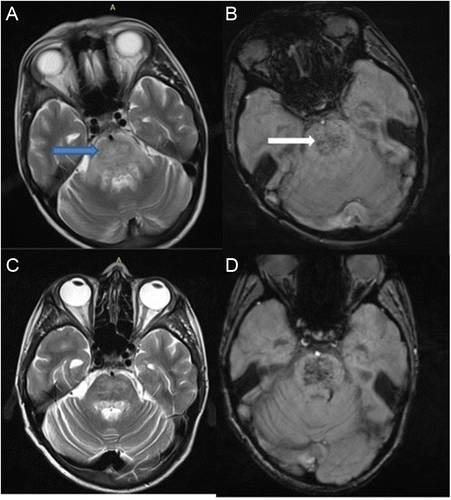

(图4:均为黑水像;中央变异型PRES

影像学表现可分为四型:顶枕型,全脑分水岭型,额上回型和中央变异型。影像学分型和水肿严重程度都不与临床表现分型和严重程度相关。额叶和颞叶受累者约占75%。累及基底节和脑干者有1/3,累及小脑者约占半数。这些部位的水肿一般是伴随着顶枕部位的受累。病变不累及顶枕区域者少见。仅累及单侧大脑和孤立性脑干与小脑水肿者需要排除其它疾病。